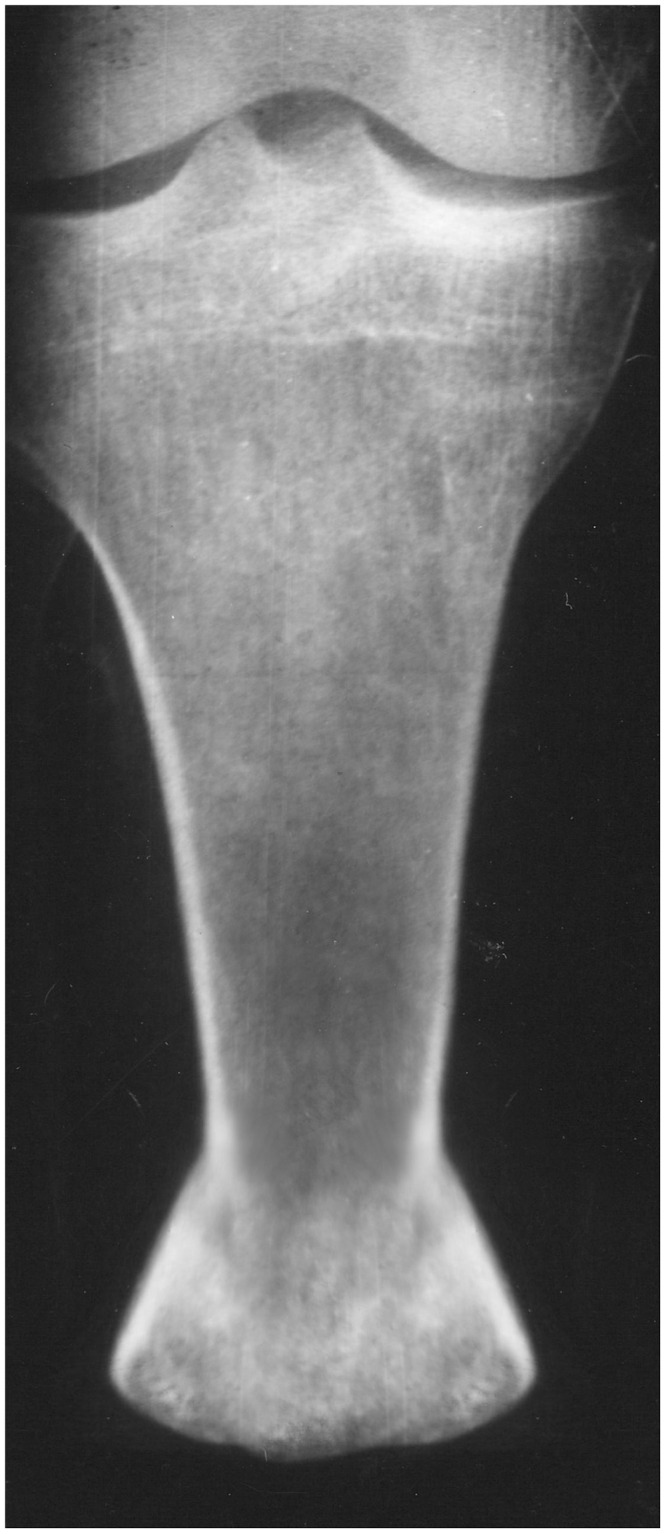

The formation of a functional tibial stump after combat injuries with extensive tissue damage is sometimes difficult. We describe a case of reconstruction of the tibial stump after a mine-blast injury. In this case, the fibula was completely removed as a result of fracture, and the tibia was amputated at the border of the upper and middle thirds. To create a stable platform with a larger bearing surface area and reduce the load on the distal fossa, the Ilizarov method was used. For the first time, the area of the bearing surface of the tibia stump was increased by more than 2 times in the case of the removed fibula. Thanks to the original surgery technique, the mushroom shape of the stump end was also obtained for the first time. In the process of prosthetics, this geometry actually increases the bearing surface area and has advantages over the Ertl technique, where the cylindrical end of the stump due to muscle atrophy and thinning of the fibro-skin lining can lead to bursitis and even ulcers. The spherical shape of the stump end causes less soft tissue trauma, increases the load-bearing capacity and durability of the results. According to the data of the GaitRite system, the walking performance in the long-term period practically corresponded to that of a healthy person. The technique of the operation is described in detail, including petal decortication, two oblique corticotomies of the tibia, formation of bone and periosteum fragments, distraction. The result is a highly functional stump with the possibility of using end support and full prosthetics. The proposed technique can be used in reconstructive operations on the tibia and femur stumps.